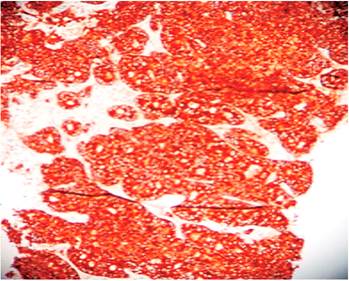

La colonoscopia reveló una lesión de aspecto tumoral a nivel de la válvula ileocecal, redondeada de unos 4 cm de tamaño y del mismo color que la mucosa circundante; se apreció el signo de la tienda de campaña, que es la elevación de la pared intestinal con base ancha y vértice romo, sin pedículo con conservación de la mucosa intacta (Figuras 3 y 4). Se tomó una biopsia para el estudio histológico, que informó la presencia de un carcinoma neuroendocrino poco diferenciado grado III. La inmunohistoquímica fue positiva a enolasa neuroespecífica (NSE), sinaptofisina y Ki 67 (Figuras 5, 6 y 7).

El diagnóstico de esta entidad debe incluir determinaciones de 5-HT en orinas de 24 horas para los carcinoides productores de serotonina, la cual no fue posible realizar por dificultades con el estudio. La TAC y resonancia magnética nuclear (RMN) han demostrado poseer similitud para el diagnóstico de metástasis regionales y a distancia con un 77 % y un 80 %, respectivamente 7; en este paciente, la TAC con doble contraste fue muy efectiva; y fue igualmente útil la endoscopia digestiva, el tránsito intestinal y el ultrasonido abdominal. Para mejorar el diagnóstico de esta entidad se usa una serie de marcadores de inmunohistoquímica, entre ellos la ENS y los marcadores asociados con vesículas pequeñas (sinaptofisina). Hay una relación casi lineal entre el tamaño y la presencia de metástasis, el 85 % de los tumores de más de 2 cm produce metástasis 5, comprobado en este paciente.